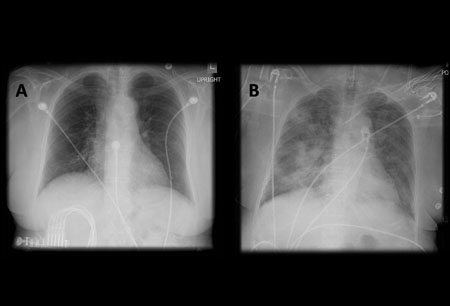

A. Переносной вертикальный рентген грудной клетки до аспирации; Б. Рентгенография грудной клетки через 1 час после аспирации, показывающая двусторонние диффузные альвеолярные инфильтраты, особенно выраженные в базальных отделах справа

Из коллекции д-ра Генри Кольта